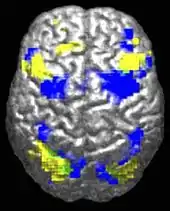

The underconnectivity theory of autism hypothesizes that autism is marked by underfunctioning high-level neural connections and synchronization, along with an excess of low-level processes.[42] Evidence for this theory has been found in functional neuroimaging studies on autistic individuals[43] and by a brainwave study that suggested that adults with ASD have local overconnectivity in the cortex and weak functional connections between the frontal lobe and the rest of the cortex.[44] Other evidence suggests the underconnectivity is mainly within each hemisphere of the cortex and that autism is a disorder of the association cortex.[45]

Functional connectivity studies have found both hypo- and hyper-connectivity in brains of people with autism. Hypo-connectivity seems to dominate, especially for interhemispheric and cortico-cortical functional connectivity.[49]